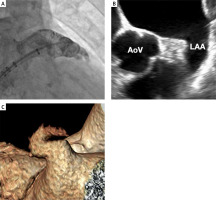

The pre-procedural use of TEE or CT is very important for optimal patient and device selection. This multimodality imaging allows to exclude LAA thrombus, determine dimensions and morphology of the LAA, and establish whether the procedure is feasible.

Precise assessment of LAA morphology is performed by 2-dimensional and 3-dimensional TEE. Transesophageal echocardiography can detect an LAA thrombus with high sensitivity (92%) and specificity (98%). Its negative predictive value reaches 100% and its positive predictive value is 86% [32]. The LAA is assessed at 0, 45, 90, and 135° to obtain its measurements and to establish the landing zone, maximum diameter, and depth.

A multidetector CT provides an accurate anatomical evaluation of the LAA and the perimeter, maximum and minimum diameter of the landing zone can be measured. Moreover, LAA thrombus can be excluded using CT imaging. It has a high sensitivity of 96% and a high negative predictive value of 100% for the assessment of thrombotic complications within the LAA [33]. Saw et al. demonstrated that CT provides the largest measurements, followed by TEE and fluoroscopy, concluding that CT more accurately assesses the true LAA dimensions [34].

The procedure is performed under general anesthesia or conscious sedation and guided by fluoroscopy and TEE or intracardiac echocardiography. The delivery sheath is introduced via the right femoral vein. The trans-septal puncture (TSP) should be performed in the postero-inferior segment of the fossa ovalis. The procedure is performed under adequate anticoagulation with unfractionated heparin (UFH) with activated clotting time > 250 s. Once trans-septal access is done, the trans-septal puncture sheath is swapped to the 14-Fr. device access sheath. The pigtail catheter is introduced into the LAA, through which the contrast is injected and angiographic projections of LAA are recorded. The Watchman device is advanced into the tip of the access sheath and the device is deployed under fluoroscopy and TEE guidance. The Watchman FLX is deployed by forming “a ball” (Figure 2) and either unsheathing while maintaining the position of the ball, or advancing the device distally out of the sheath until it is fully deployed. A combination of both of these techniques is possible. Too proximal position of the Watchman FLX can be corrected with the partial recapture thanks to the ball technique implantation. Before the device is released, the “PASS criteria” need to be fulfilled. P: optimal position of the device, A: checking anchor to the LAA by tug test, S: sealing assessed with color Doppler, and S: sizing for proper compression of the device.